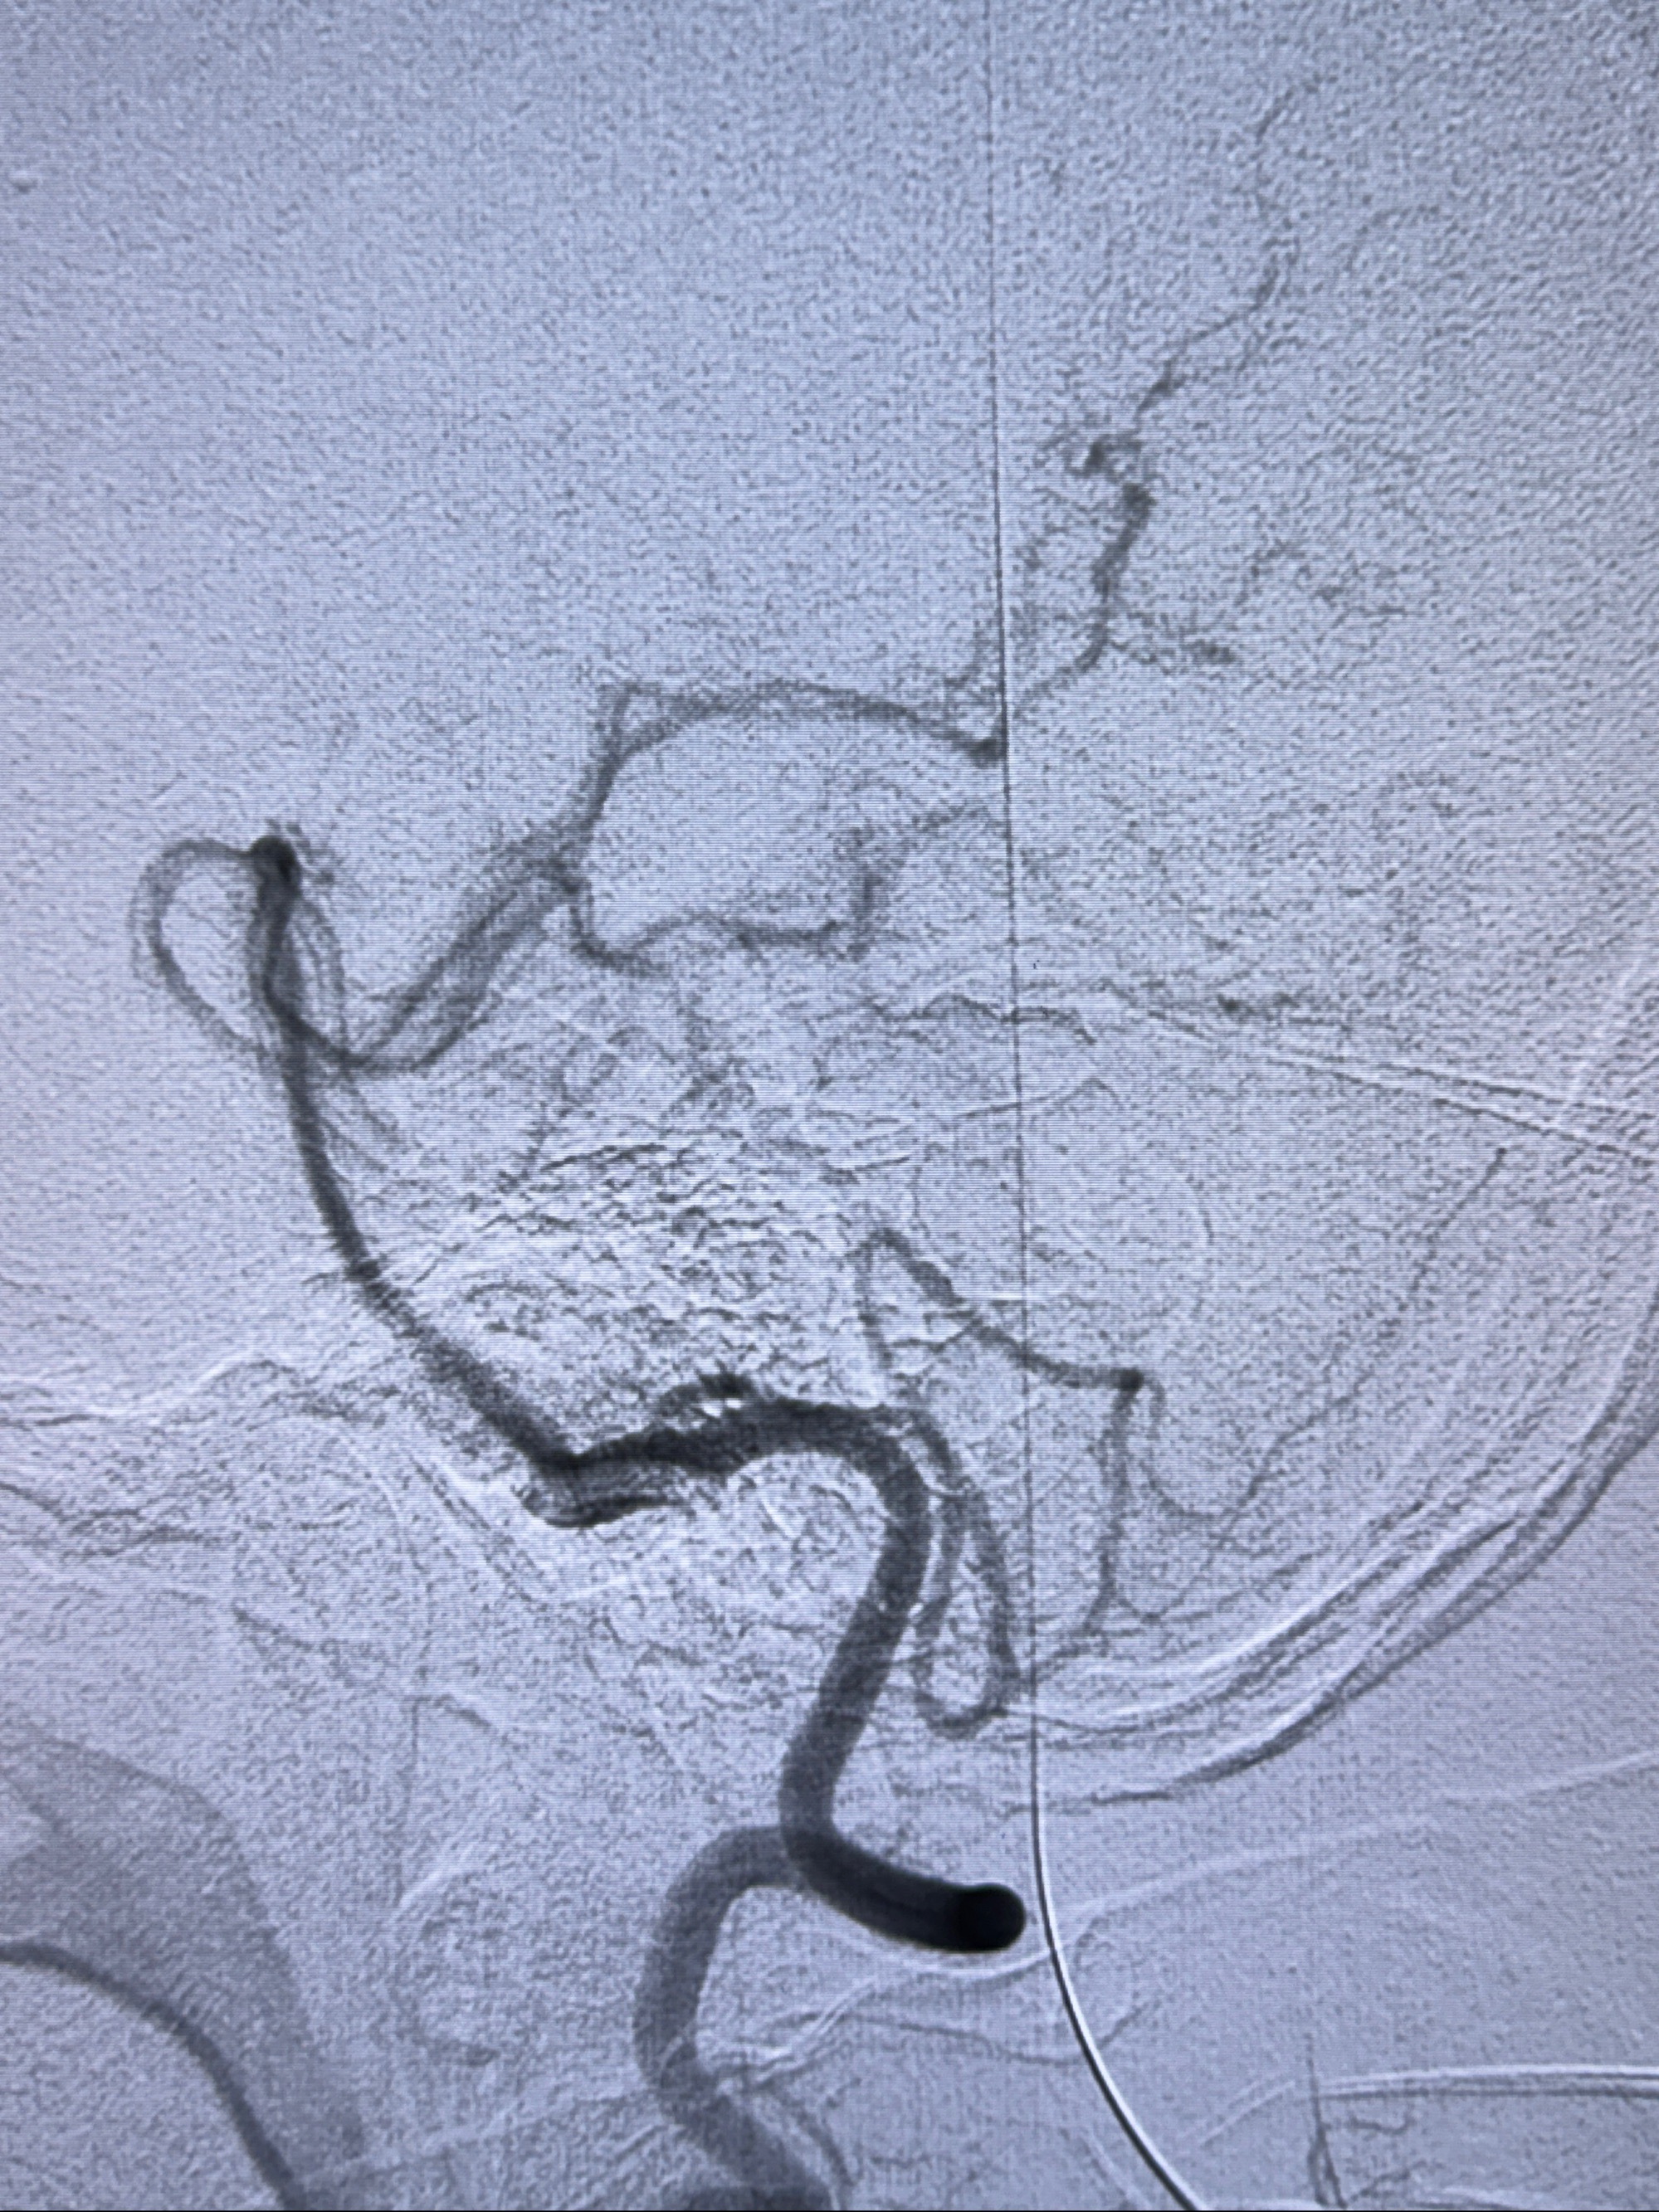

2023-11-24DSA:右侧大脑中动脉下干起始部动脉瘤,约2.3*2.5mm,形态规则

2023-12-04全麻下行支架辅助治疗

S-AB4-20mm

麻醉苏醒佳,遵嘱动作